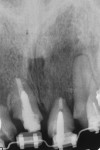

The orthodontist began treatment that would entail eruption of the four involved teeth of approximately 0.5 mm to 1 mm per month.10 This would allow for optimal ridge development of the bone. At each visit, the orthodontist would shorten the length of the provisionals to allow for further extrusion. The orthodontist completed treatment in 5 months, and the teeth were stabilized with a rectangular archwire (Figure 6 and Figure 7). The patient was then referred to the periodontist for the extractions of teeth Nos. 7 through 9 and implant placement.

The plan was to place implants in either sites Nos. 7 and 9 or sites Nos. 8 and 9, whichever would prove to be the better option after the extractions. The teeth were extracted and the sites were evaluated (Figure 8 and Figure 9). One of the concerns before orthodontic extrusion was the apical lesions on teeth Nos. 7 through 9 and their potential effect on the amount of bone augmentation as the teeth erupted. Although site No. 7 had excellent bone, the presence of a large apical lesion would make it difficult to place a fixture there immediately. Sites Nos. 8 and 9 had excellent bone, and thus these sites were chosen for implant placement. Immediate implant placement was accomplished.11,12 Gaps between the implants and bone were filled with a mixture of particulate bone and calcium sulfate, and healing abutments were placed.

The large apical lesion on No. 7 was debrided, and the extraction socket was filled with a mixture of bone mineral substitute (BioOss®, Geistlich Biomaterials, dental.geistlich-na.com) and calcium sulfate and covered with a resorbable membrane (Figure 10).13 The patient left the periodontist's office and went to the orthodontist who placed a fixed wire temporary provisional to replace Nos. 7 through 9 and ligated it in place (Figure 11 and Figure 12). The patient healed uneventfully. The healing abutments and bone grafting in the gaps maintained a thick labial contour.